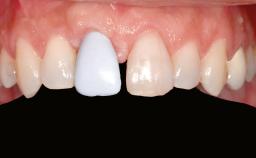

A 20-year-old woman was referred for implant therapy in 2004. Her medical history revealed no significant findings, and neither did she smoke nor take any medications. An extraoral examination revealed no abnormalities of the skin, hair or nails. The intraoral examination revealed only 11 permanent teeth clinically. These were normal in shape, size, and color. In addition, eight retained deciduous teeth (53, 62, 63, 71, 72, 73, 81, 82) were present. No abnormalities were detected during the general examination. The family history revealed that the patient’s father and two sisters were on record with similar conditions. The clinical examination revealed a thick gingival biotype. No recession of the attached gingiva was noted, but the retained deciduous teeth were mobile and unsightly. As a syndrome had not been diagnosed, the case was categorized as non-syndromic oligodontia.

Shape of Tooth Crowns Rectangular Triangular

Soft Tissue Anatomy Intact Defective